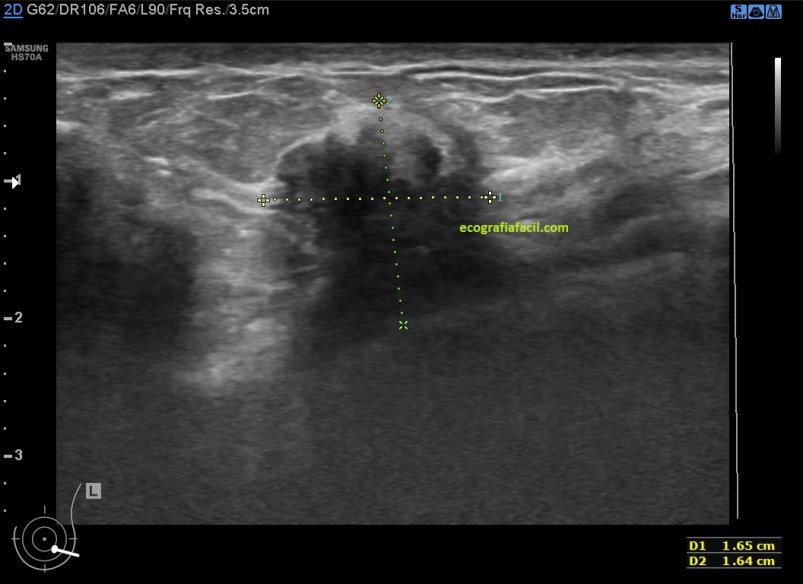

El estudio ecográfico mostró:

1. Mamas de predominio fibroso.

2. Acúmulos de tejido asímétricos de tejido fibroso de aspecto altamente denso e hipoecogénico de contorno mal definido en ambas mamas con ausencia de doppler color.

3. Mastopatía Diabética

4. Mastopatía Diabética

5. Mastopatía Diabética

6. Mastopatía Diabética. Doppler Color.

De la imagen 3 a la 6 tienes el aspecto semiolólogico normal de una mama diagnosticada de Mastopatía Diabética.